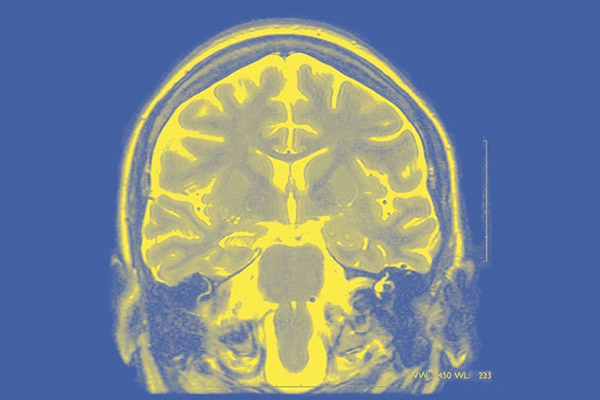

تم ابتكار نظام الكتروني يطور نماذج رقمية تمثل أدمغة المصابين بالصرع أن ترشد جراحي الأعصاب بشكل محدد إلى المناطق المسؤولة عن نوبات الصرع، ما يتيح علاجًا أفضل. جرى تطوير النماذج، التي ابتُكرت بواسطة نظام حاسوبي يعرف باسم «مريض الصرع الافتراضي» Virtual Epileptic Patient، بوصفها جزءًا من «مشروع الدماغ البشري».

وذكر الطبعة العربية لمجلة نيتشر في عددها الجديد أن «مشروع الدماغ البشري» عبارة عن مبادرة علمية أوروبية انطلقتْ منذ عشر سنوات تركز على أبحاث الدماغ الرقمية.

وأضافت المجلة أن هذا النهج يُختبر في تجارب إكلينيكية لتقييم ما إذا كان يحسّن معدلات نجاح جراحات الصرع.